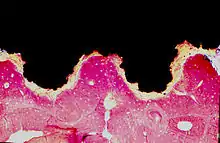

Titanium implant (black) integrated into bone (red): Histologic section

Osseointegration was first observed—albeit not explicitly stated—by Bothe, Beaton, and Davenport in 1940.[3][4] Bothe et al. were the first researchers to implant titanium in an animal and remarked how it tended to fuse with bone.[3][4] Bothe et al. reported that due to the elemental nature of the titanium, its strength, and its hardness, it had great potential to be used as future prosthesis material.[3][4] Gottlieb Leventhal later described osseointegration in 1951.[3][5] Leventhal placed titanium screws in rat femurs and said, "At the end of 6 weeks, the screws were slightly tighter than when originally put in; at 12 weeks, the screws were more difficult to remove; and at the end of 16 weeks, the screws were so tight that in one specimen the femur was fractured when an attempt was made to remove the screw. Microscopic examinations of the bone structure revealed no reaction to the implants, the trabeculation appeared to be perfectly normal."[3][5] The reactions described by Leventhal and Bothe et al. would later be coined into the term "osseointegration" by Per-Ingvar Brånemark of Sweden. In 1952, Brånemark did an experiment where he used a titanium implant chamber to study blood flow in rabbit bone. At the end of the experiment, when it became time to remove the titanium chambers from the bone, he discovered that the bone had integrated so completely with the implant that the chamber could not be removed. Brånemark called this "osseointegration", and, like Bothe et al. and Leventhal before him, saw the possibilities for human use.[3][4][5]